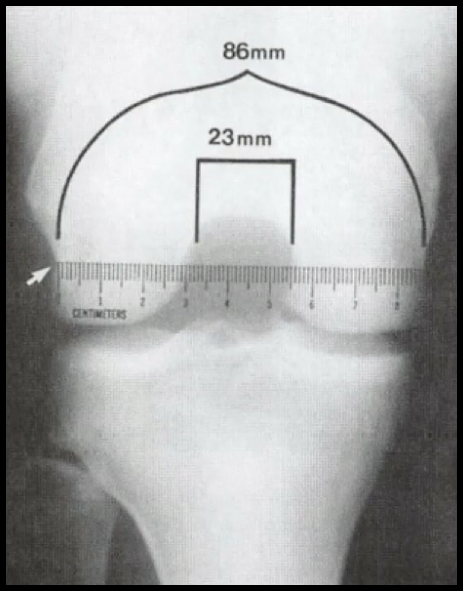

• Estenose do Notchin Intercondilar

Sexo Feminino → Estenose do Notching e Frouxidão